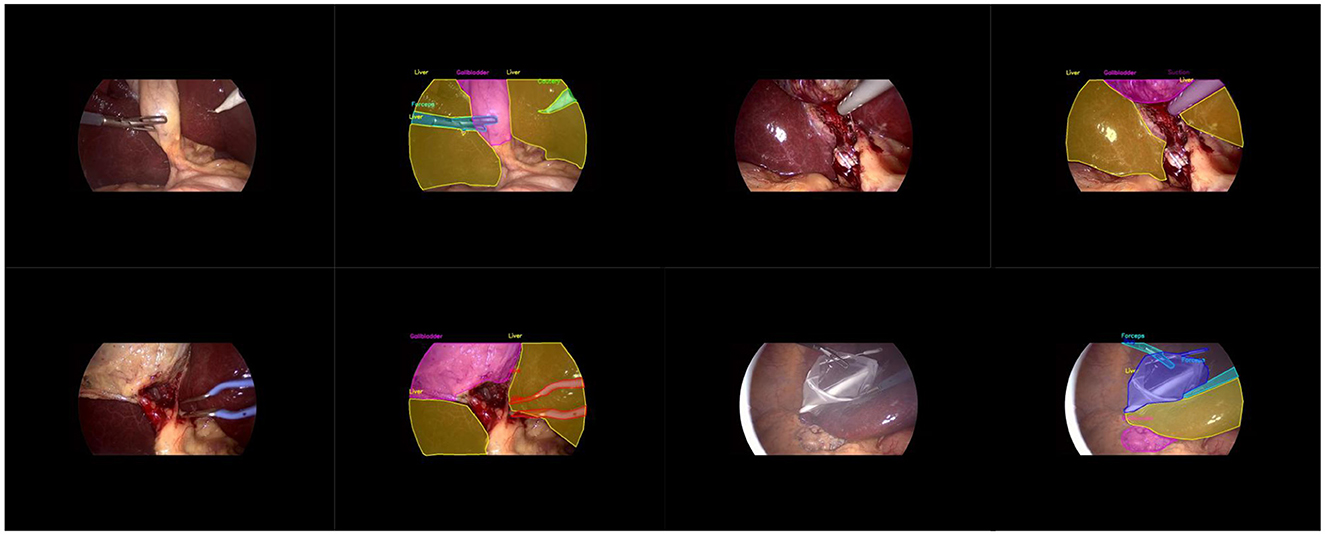

LC-YOLOmatch: A Novel Scene Segmentation Approach Based on YOLO for Laparoscopic Cholecystectomy

Laparoscopy is a visual biosensor that can obtain real-time images of the body cavity, assisting in minimally invasive surgery. Laparoscopic cholecystectomy is one of the most frequently performed endoscopic surgeries and the most fundamental modular surgery. However, many iatrogenic complications still occur each year, mainly due to the anatomical recognition errors of the surgeons. Therefore, the development of artificial intelligence-assisted recognition is of great significance. This paper proposes a method based on the lightweight YOLOv11n model. By introducing the efficient multi-scale feature extraction module DWR, the real-time performance of the model is enhanced. Additionally, the bidirectional feature pyramid network (BiFPN) is incorporated to strengthen the capability of multi-scale feature fusion. Finally, we developed the LC-YOLOmatch semi-supervised learning framework, which effectively addresses the issue of scarce labeled data in the medical field. The experimental results on the publicly available Cholec80 dataset show that this method achieves 70% mAP50 and 40.8% mAP50-95, reaching a new technical level and reducing the reliance on manual annotations. These improvements not only highlight its potential in automated surgeries but also significantly enhance the assistance in laparoscopic procedures while effectively reducing the incidence of complications.